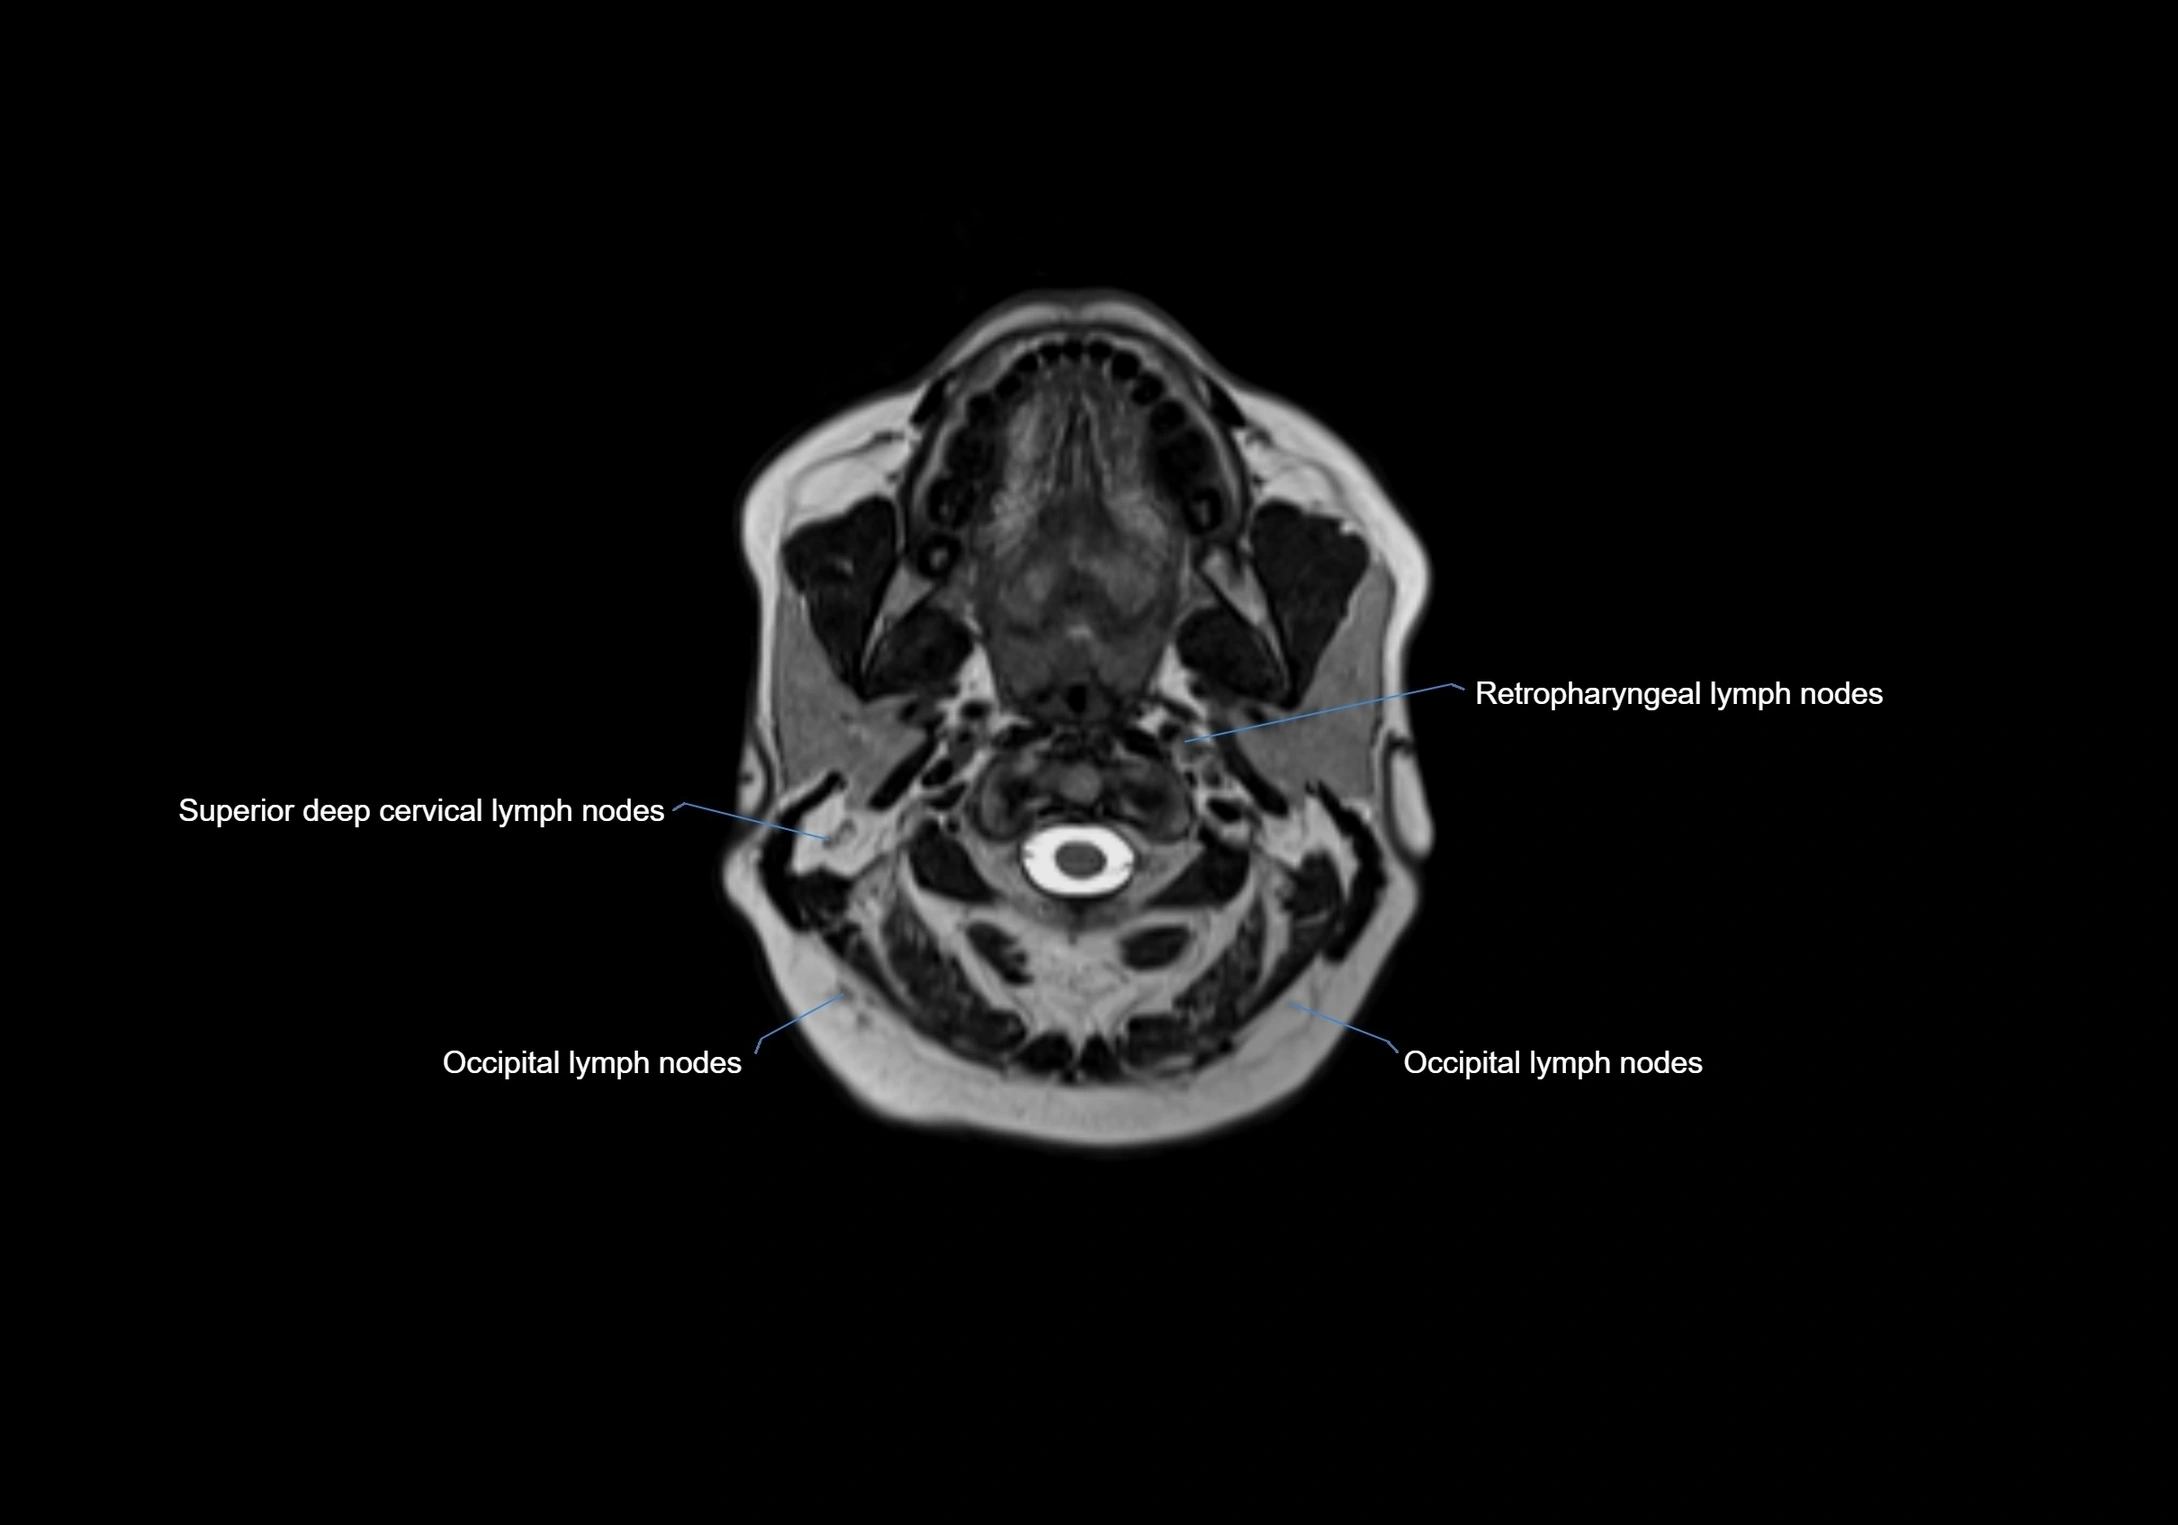

MRI Appearance

T1-weighted images:

• Normal accessory nodes appear as small, oval hypointense to intermediate signal structures within subcutaneous fat

• Surrounded by hyperintense fat, enhancing contrast for visualization

• Pathological nodes may appear enlarged or rounded, sometimes with cortical thickening

T2-weighted images:

• Nodes show intermediate signal, with surrounding fat bright

• Useful for detecting edema, inflammation, or infiltration

• Fatty hilum may appear slightly hyperintense relative to cortex

MRI images

image